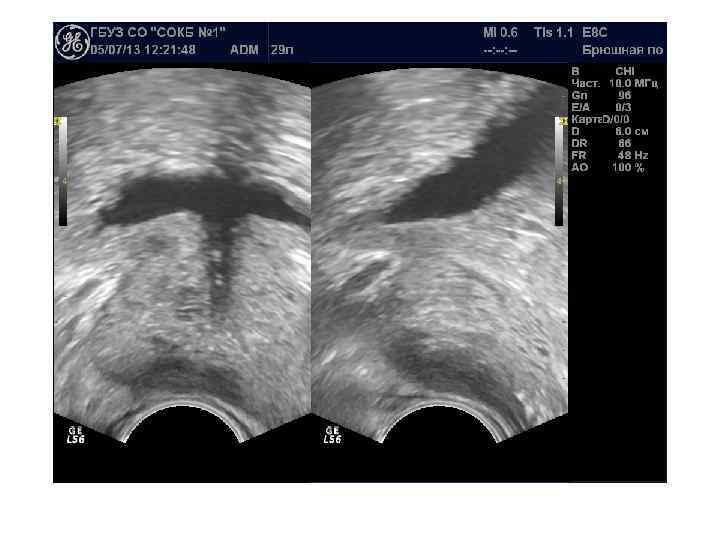

При ДГПЖ меняются форма, размеры, структура и соотношение частей железы. Форма становится шаровидной или неправильной с выбуханием контура в просвет мочевого пузыря. При росте переходных зон происходит значительное увеличение размеров, но это не приводит к выраженной обструкции уретры. При росте периуретральных желез простата увеличена незначительно, но происходит сдавление уретры выбухающей средней долей. Структура гиперплазированных узлов неоднородная, часто с дегенеративными изменениями ( кисты, участки склероза, кальцификаты).

Если происходит преимущественный рост переходных зон, образуются латеральные доли. Зональная анатомия предстательной железы при ДГПЖ. При ДГПЖ увеличивается объем переходной зоны (Tz), размеры центральной зоны (Cz) и периферической зоны (Pz) уменьшаются. Vm — семенной бугорок, А — фибромускулярная строма.